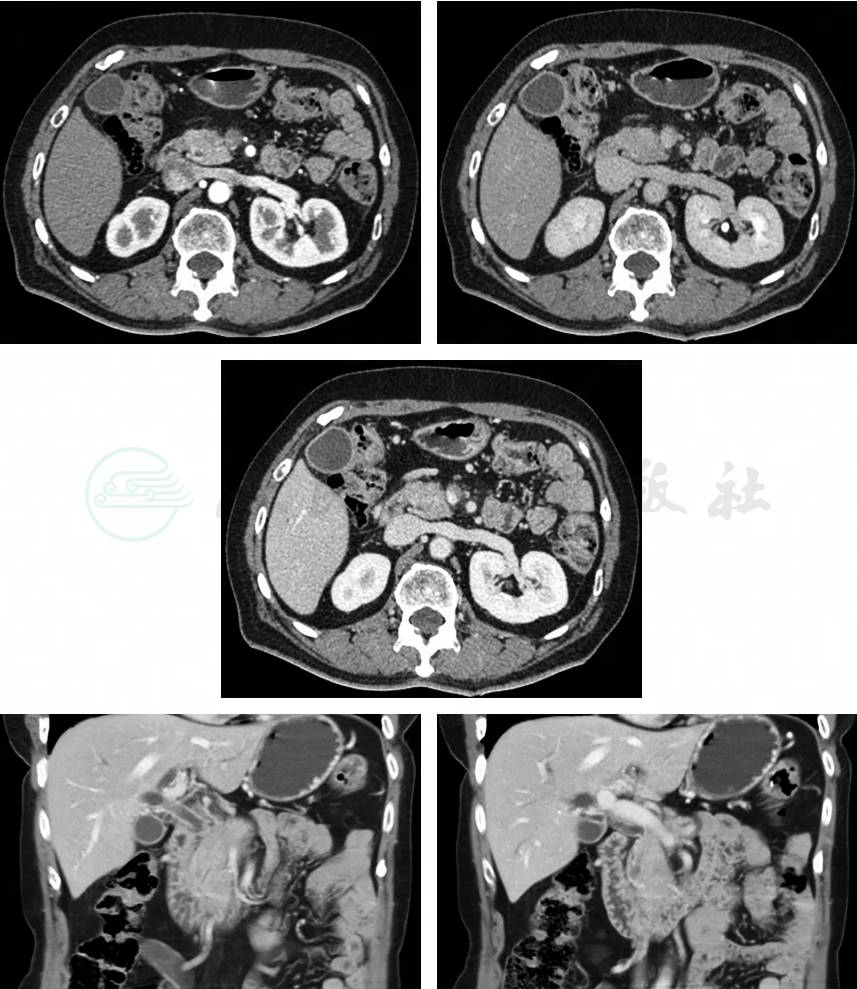

口服甲泼尼松 24mg/d,起效后缓慢减量(图3)。

图3 用药1周后磁共振检查

用药4周后涎腺超声检查:左侧厚约1.7cm,右侧大小约1.2cm,双侧颌下腺结构不清,回声不均。腹部超声检查:胰腺头部形态饱满,局限回声减低,范围约3.8cm×2.5cm×1.1cm,边界欠清,回声不均。CA19-9正常。TBil 83.3μmol/L,DBil 63μmol/L,给予拔除PTCD。造影提示胆管肝门汇合部狭窄已基本消失,肝内胆管无扩张(图4)。用药8周后 TBil 20μmol/L,DBil 13.3μmol/L。

图4 用药4周后,拔除PTCD时造影